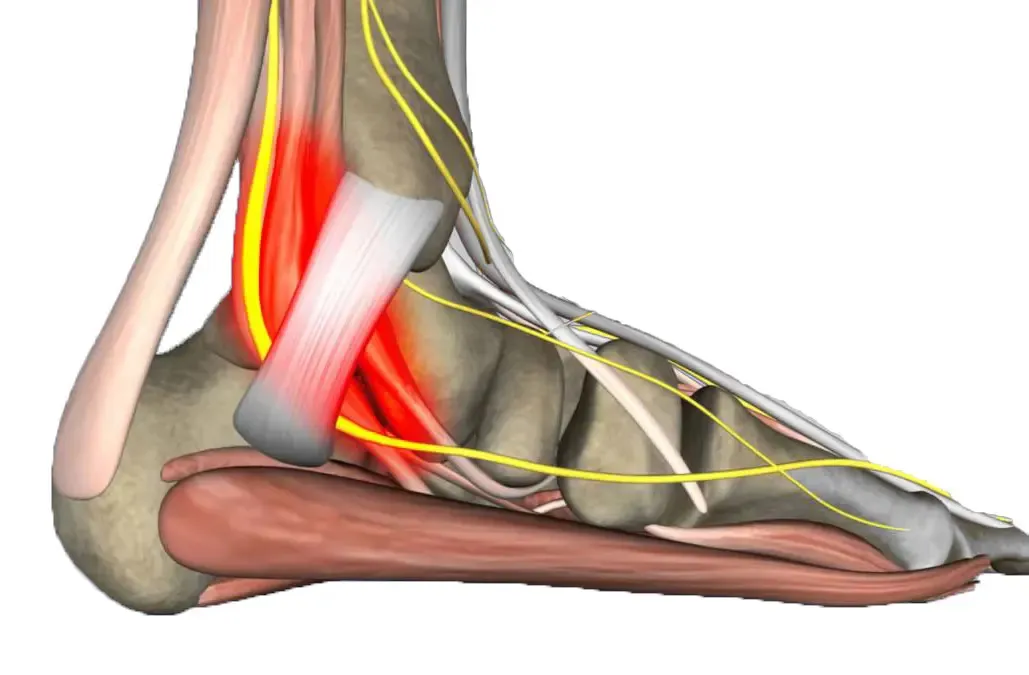

Atrapamiento de Baxter

El atrapamiento del nervio de Baxter ocurre cuando el nervio tibial posterior se comprime al pasar por el túnel del tarso, causando dolor plantar. Es una condición que puede confundirse fácilmente con la fascitis plantar.

Tendinopatía aquílea

La tendinitis del tendón de Aquiles es una causa frecuente de dolor en la parte posterior del talón. El dolor generalmente se intensifica al caminar o realizar actividades físicas que sobrecargan el tendón.